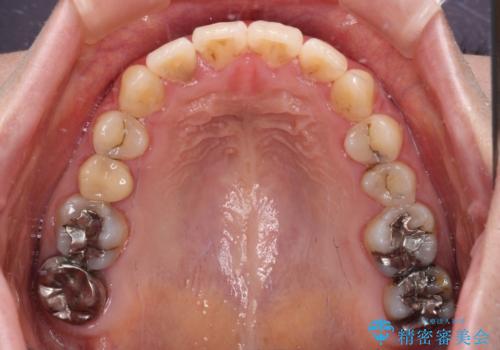

- 捻れた前歯が飛び出しており、口が閉じにくいとのことで来院された患者様です。

出っ歯というわけではないものの、前歯の捻転により口唇が押し出されている状態でした。

親知らずを抜去し、歯列全体を後方に移動させつつ、IPR(歯と歯の間を削る)でスペースを獲得し、インビザラインを用いて叢生を解消しながら前歯の突出を改善することとしました。

インビザラインは、患者様の協力無しには成立しない治療ですが、しっかりと装着時間を遵守してくださり、1年弱で治療を終えることができました。